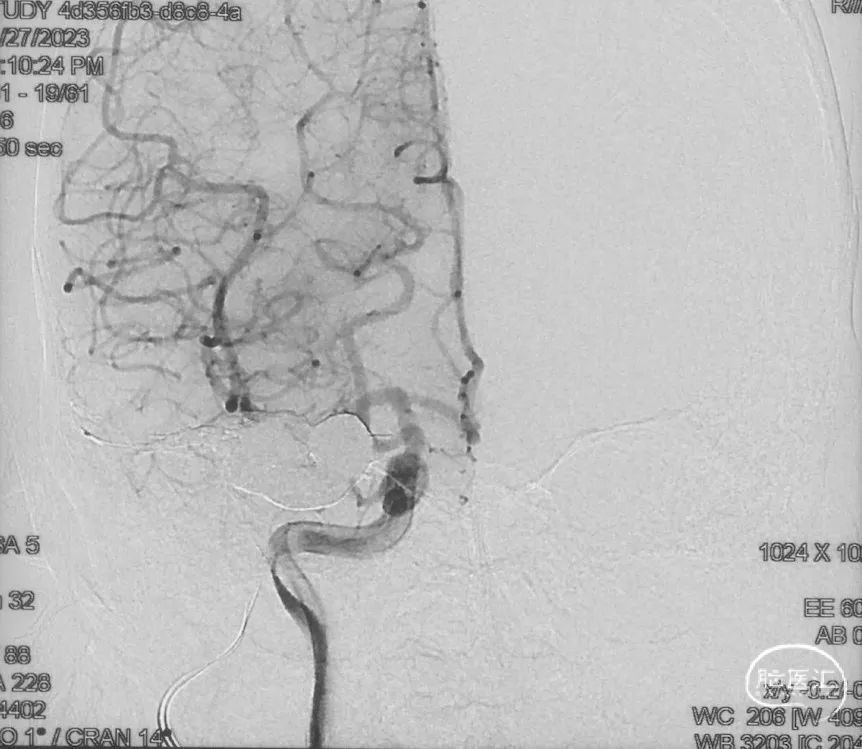

Echelon-10微导管在ASAHI 0.010微导丝导引下经右侧脑膜中动脉分支超选至瘘口,可见瘘口口径大,微导管直接越过瘘口,进入引流静脉起始部。

Marathon微导管在ASAHI 0.010微导丝导引下经右侧脑膜中动脉分支超选至瘘口近端。

经Marathon微导管手推造影明确微导管位于瘘口动脉端,Echelon-10微导管位于瘘口引流静脉起始端处扩张的静脉球内。

由于瘘口流量大,为了防止栓塞材料过度弥散,并逃逸至深静脉,首先通过Echelon-10微导管向静脉球内填入Feng 12/40、Feng 10/30两枚弹簧圈,限制后续液态栓塞材料仅在静脉起始部弥散。

随后回撤Echelon-10微导管,并通过Echelon-10微导管和Marathon微导管交替注入Onyx-34、Onyx-18,此时可见Onyx首先被血流冲至静脉球内,但被弹簧圈篮筐限制,并在瘘口范围内弥散。

通过“注射-停顿-再注射”,Onyx进一步在瘘口及供血动脉段和引流静脉起始部弥散满意

造影显示瘘口不显影,无静脉早显。